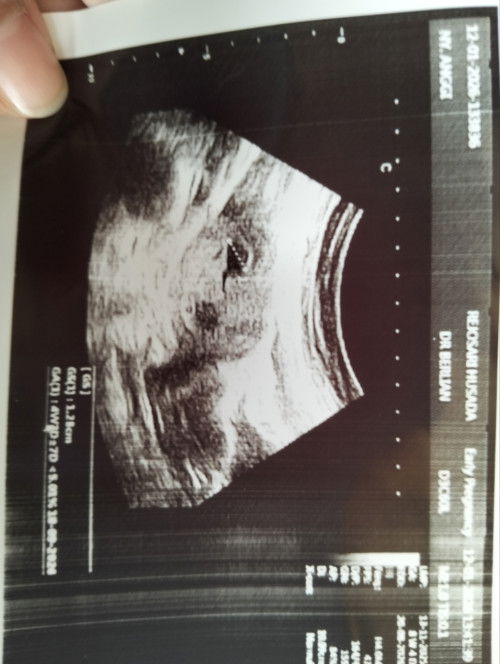

Usg 8 minggu

Jadi galau karena baru kelihatan kantungnya padahal udah 8minggu, kira2 bunda juga pernah mengalami tidak?#mohonbantujawabbunda

Đã trả lời 4mo trước bởi Ni Nyoman Sri Jayantri

kl aku kemarin ke dr 7 minggu 1 hari blm ada kantongnya bun.. jujur bimbang bgt😩